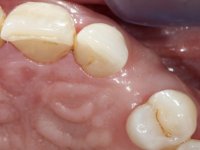

To define the dental zone to be covered by the Maryland bridge retainers, the patient was asked to perform maximum intercuspidation movements, and the contact points were marked with articular paper. Tooth preparation of the interproximal surfaces was made, to create a prosthetic insertion axis. It was sought that the mesio-distal diameter at the incisal level was equal to the diameter mesio-distal at the cervical level, that is to say, the interproximal walls were parallelized. Tooth preparation was done with fine grain diamond drills, and later polishing was done with abrasive discs. Color information was collected even before confection of the impression, to avoid dehydration of the arcade. Definitive impression was made using wash technique impression with silicone of heavy and regular consistency, both with fast setting, and a working plaster model was prepared in the lab. A laboratory scanner was used to scan the working model, and later, the infrastructure for the Maryland bridge was made using a CAD-CAM process. Ceramic was placed on this subframe. A ceramic adhesive was applied to the internal surface of the wings and connectors, which would enable bonding to the adjacent teeth. The adhesive bridge was bonded in the mouth following the conventional bonding technique. After bonding, the protrusion and laterality movements were carefully checked to avoid undesirable contacts.